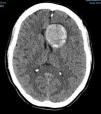

Más datosMujer de 49 años que sufrió una primoconvulsión. Se realizó una TC de cráneo (fig. 1) que objetivó un aneurisma gigante en la arteria carótida interna (ACI) izquierda, trombosado de forma subtotal (no captaba contraste en el angio-TC). Se decidió realizar una arteriografía (fig. 2) que describía un gran aneurisma carótido-oftálmico izquierdo, con una mínima porción permeable (8×5mm), el resto lo describen trombosado. Durante la arteriografía hizo focalidad con hemiparesia y desviación de comisura vocal, con vasoespasmo arteriográfico, que cedió tras administrar verapamilo. Se realizó una RM (fig. 3) que describía el aneurisma con localización paraselar frontal izquierda de 4,2×3,9×3,6cm con origen en el top de la ACI izquierda, presentando efecto masa sobre ambas arterias cerebrales anteriores, arteria cerebral media izquierda, así como compresión y desplazamiento derecho de ambas astas frontales. En el estudio de angio-RM se delimitó una dilatación sacular de 9mm en la porción supraclinoidea de la ACI izquierda, localizada en el tercio inferior del seno de la lesión descrita. Sugieren diagnóstico diferencial con rotura contenida del aneurisma. Se decidió intervención quirúrgica de clipado del aneurisma, que confirmó trombosis parcial del mismo con cápsula íntegra. Tras esto, la paciente se encuentra sin focalidad y como única complicación posterior ha desarrollado un síndrome pierde-sal.